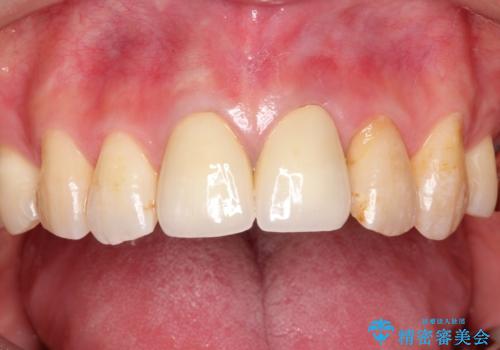

変色した前歯をセラミックできれいに レイヤリングセラミック

前歯のセラミック治療では、他の歯と色調をそろえるのが非常に難しいです。

他の歯に亀裂や白濁など複雑な色合いがある場合、それらをセラミックで再現することも可能ですが、スタンダードのオールセラミックではある程度の同調となります。

かぶせ物の種類: PFZ standard